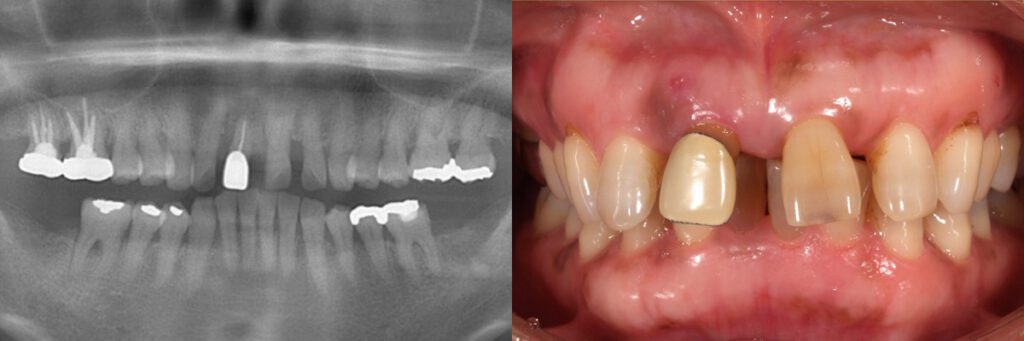

初診時

インプラント治療は、診査・診断・治療計画が全てです。フリーハンドでインプラントを埋入するのではなく、3Dシミュレーションを行い、計画的に間違いの起こらないよう埋入することが肝心です。

自分の施した治療の結果を10年、20年と追跡して、そこから学び、日々技術を高めていくために治療前後の症例写真をはじめ、徹底した臨床記録を管理する必要があります。